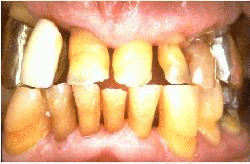

Varón de  63 años de edad con  enfermedad periodontal severa. Los dientes se han desgatado severamente y al sondaje de las bolsas periodontales encontramos una profundidad de  6-8 mm. En el canino inferiór puede observarse un épulis. Las señales de inflamación severa están presentes. La condición necesita tratamiento quirúrgico  con  gingivectomía, raspaje y alisado radicular. El paciente es instruído en los procedimientos de higiene oral.